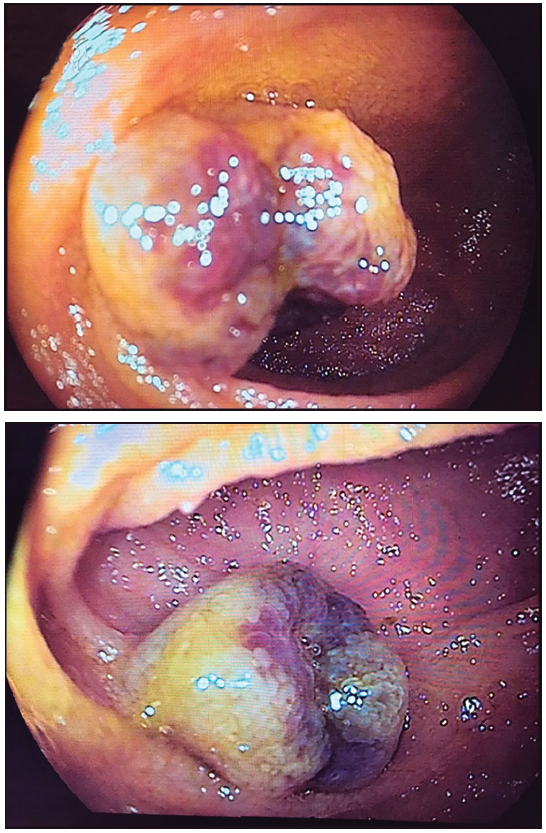

Hombre de 17 años, derivado para el estudio de hemorragia de intestino medio. Presentaba antecedentes de anemia ferropénica de años de evolución, con requerimientos transfusionales de glóbulos rojos y en tratamiento con hierro endovenoso. Al interrogatorio, refirió astenia, sin dolor abdominal y sin evidencia de sangrado digestivo. Al ingreso, se encontraba hemodinámicamente estable, afebril, con abdomen blando depresible, indoloro y sin evidencia de masa palpable. Presentaba serologías negativas para enfermedad celíaca, videoendoscopía digestiva alta (VEDA) normal y videocolonoscopía (VCC) con ileoscopía y adecuada preparación (escala de limpieza colónica de Boston 9/9) sin evidencia de lesiones. En el análisis bioquímico, se constató hemoglobina de 10 mg/dl, con perfil de hierro compatible con ferropenia. Se decidió estudiar el ID con VCE (Capsocam®). Se realizó estudio completo de ID, con adecuada preparación, observándose múltiples lesiones elevadas lobuladas violáceas, de 5 a 15 mm de diámetro; la mayor estaba ubicada en el íleon terminal, siendo compatibles con hemangiomas múltiples (Vídeo 1). Se descartó la presencia de hemangiomas cutáneos y en otros órganos internos, mediante la evaluación clínica, por el servicio de dermatología y estudios por imágenes. Dado que la lesión de mayor tamaño se ubicaba en el íleon terminal según la VCE, se realizó ileocolonoscopía (Olympus® serie CF-H180AL). A 30 cm de la válvula ileocecal, se evidenció lesión elevada lobulada, de color azulado, de 30 mm de diámetro, sin signos de sangrado activo.

A los seis meses del tratamiento, intercurrió con un nuevo episodio de anemia sintomática. Se realizó enteroscopía anterógrada con doble balón (Fujinon® serie EN-450T5), sin evidencia de lesiones, con marcación del sitio de máxima inserción y enteroscopía retrógrada, evidenciandose en ileon, proximal a la cicatriz del tratamiento previo (Figura 2) una lesión similar a la anterior (Figura 3), de 25 mm de diámetro. Se realizó escleroterapia con polidocanol al 1% (seis mililitros), sin complicaciones.